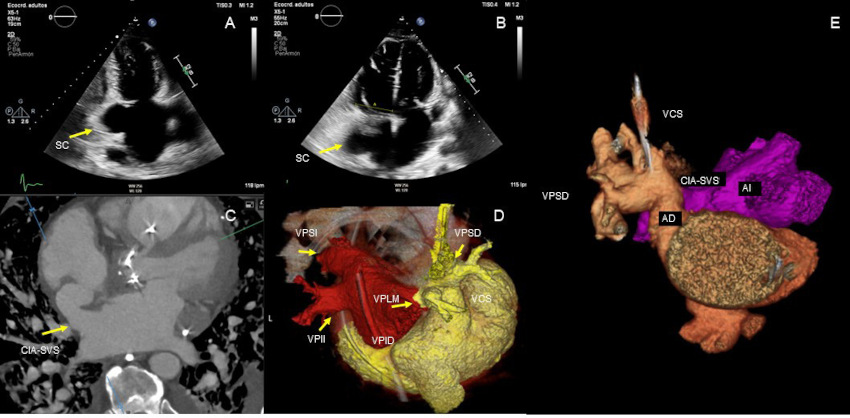

Varón de 69 años, con antecedentes de sustitución de válvula aórtica bicúspide se presentó con insuficiencia cardíaca derecha progresiva. La ecocardiografía transtorácica reveló dilatación y disfunción grave de las cavidades derechas, con sospecha de cortocircuito (shunt) interauricular (Fig 1A-B). La ecocardiografía transesofágica (ETE) identificó una intercomunicación interauricular de tipo seno venoso superior (CIA-SVS), dilatación del seno coronario (SC) y persistencia de la vena cava superior izquierda (PVCSI) con ausencia de drenaje de la vena pulmonar superior derecha en la aurícula izquierda

La tomografía computarizada (TC) cardíaca confirmó la CIA-SVS y reveló una PVCSI que drenaba en un seno coronario dilatado. Asimismo, se observó un drenaje venoso pulmonar anómalo parcial (DVPAP) de la vena pulmonar superior derecha y de una vena accesoria del lóbulo medio hacia la vena cava superior (Fig. 1C-E). También se observó dilatación del tronco pulmonar, hallazgo compatible con hipertensión pulmonar.

Fig. 1

Ecocardiograma transtorácico que muestra un seno coronario dilatado (SC) (A) y un marcado agrandamiento del ventrículo derecho (B). La TC cardíaca muestra una comunicación interauricular del seno venoso superior (CIA-SVS) (C). Reconstrucción tridimensional de la TC cardíaca que muestra las venas pulmonares superior izquierda (VPSI), inferior izquierda (VPII) e inferior derecha (VPID) drenando en la aurícula izquierda (AI), mientras que la vena pulmonar superior derecha (VPSD) y la vena pulmonar accesoria del lóbulo medio (VPLM) drenan de forma anómala en la vena cava superior (VCS) (D-E).